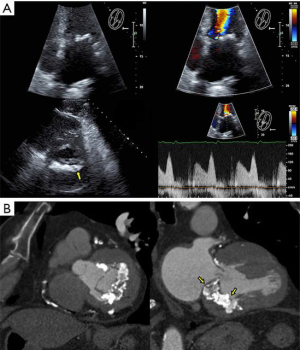

- The mitral annulus (MA) is mathematically represented as a hyperbolic paraboloid, with a higher anterior peak included in the aorto-mitral curtain, a lower posterior peak and two fibrous trigones, representing its lateral and medial nadirs. The flat anterior annulus is the least mobile portion, in contrast to the rounded posterior aspect, which is more “contractile”. Due to this dynamic shape, MA may be difficult to characterize. Defined as the leaflet insertion zone, the anterior annulus is cranial to the actual hinge point of the anterior mitral leaflet (AML), due to the fibrous substrate of the aorto-mitral curtain, which extends below leaflet insertion (Figure 1). In patients with myxomatous degeneration, the leaflet insertion may be displaced above the annulus, resulting in “mitral disjunction” (Figure 2, Video 1) (1). Distinguishing between the MA and AML hinge point may be relevant for transcatheter mitral valve (TMVR) procedures. MA geometry changes during the cardiac cycle. In systole, the annulus descends apically, becomes more vertical and increases its anteroposterior diameter. The saddle shape is accentuated, which reduces leaflet strain. In diastole, the annulus becomes more horizontal, shrinks its area and flattens. The aorto-mitral coupling determines the angle between aortic and mitral annuli, a critical parameter for predicting left ventricular outflow tract (LVOT) obstruction following TMVR. The mitral annulus “trajectory”, defined as a vector orthogonal to the annulus “plane”, commonly diverges from the left ventricular longitudinal axis and determines the site for transapical device delivery (Figure 1). Lastly, the posterior MA tends to be less compliant, resulting in asymmetric, typically anterior, deployment of TMVR devices. Locating the MA during a procedure may require visual aids: an angiogram of the left circumflex artery, mitral annulus calcification (MAC) noted on fluoroscopy, or a guidewire deployed in the coronary sinus.

- CT, compared to echocardiography, lacks hemodynamic data, has lower signal to noise ratio, comparable temporal resolution and better spatial and contrast resolution, making it suitable for MV imaging (10). Operator-dependent, optimized imaging protocols for MV include: wide field of view, higher peak kV, bolus timing using time attenuation curves, left atrial contrast target, 5–10% phase intervals and specific reconstructions for annulus sizing and LVOT analysis (11). Image analysis is performed on the thinnest possible slice, using projections similar to echocardiographic views, with 4D reconstructions and multiplanar reformatting adjusted to minimize beam hardening and blooming effect. Lifelike, 4DCT cinematic rendering may be more useful compared to traditional 3D volumetric reconstructions. CT is indispensable for mitral annulus sizing and for the prediction and evaluation of LVOT obstruction risk in TMVR (Figure 3, Video 2) (10,12-22). Additionally, CT allows precise measurement of the geometric mitral valve area, predicts optimal fluoroscopic angles and identifies the location of the coronary sinus in relation with the annulus (Figure 4). Accurate sizing of the MA is critical for device choice. The least square planes method projects the 3D contour of the annulus on to a 2D plane and led to the concept of a simplified, flat, D-shaped mitral annulus, which reflects the actual planar landing zone of TMVR devices (6,23,24). A reproducible “effective annular diameter” can be derived from either the measured area, or the perimeter of the annulus (12). CT is vastly superior to echocardiography in imaging mitral annulus calcification (MAC), which can disrupt the atrioventricular groove and extend into the leaflets or the adjacent myocardium. Extensive leaflet calcification or fibrosis represents the basis of “degenerative MS” (Figure 5). MAC may involve the adjacent myocardium, or display a “caseous” core, without significant MS (Figure 6). TMVR creates a “neo-LVOT” between the basal segment of the interventricular septum and the AML, displaced anteriorly by the prosthesis struts, or flange (25). The semilunar cross-sectional area of the neo-LVOT may be measured by planimetry. Since LVOT obstruction may have profound hemodynamic consequences, several methods have been proposed to predict the risk of this complication, including proprietary software (11,24-26). Predictors of LVOT obstruction can be identified by CT, TTE or TEE: aorto-mitral angle <110°, LVOT area <2.0 cm2, length of the AML, short chordae, direct papillary muscle attachment, thickness of the basal segment of the interventricular septum and LV cavity size.